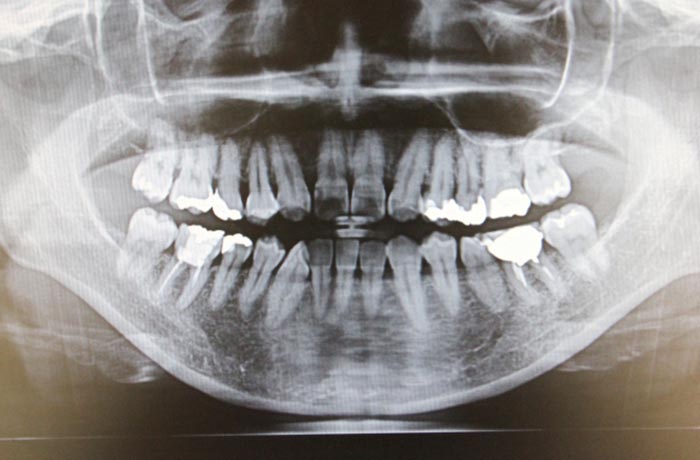

現在の歯科医院では、デジタルレントゲン、口腔内カメラ、CAD/CAMシステム、3Dスキャナーなど、様々なデジタル機器が導入されています。しかし、多くの医院で「機器は導入したが十分に活用できていない」「期待した効果が得られない」といった課題が発生しています。

特に、口腔内カメラやデジタルレントゲンなど、患者への説明に直接活用できる機器は、患者満足度向上と自費診療成約率向上の両方に寄与するため、ROIが高くなる傾向があります。